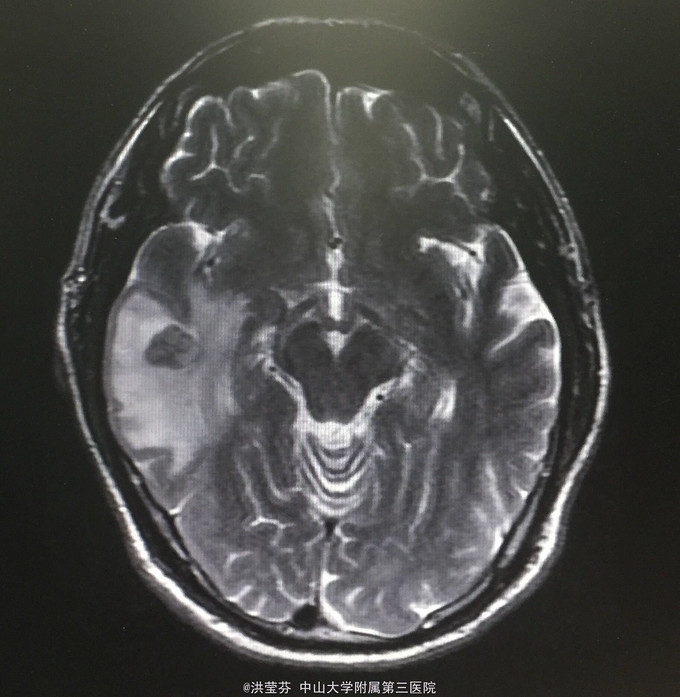

查体:KPS 60分,BSA 1.83m2,T 38.5℃,全身浅表淋巴结未触及明显肿大,胸壁可见浅表静脉曲张,呼吸急促,左下肺、右中下肺呼吸音明显减弱,其余肺野呼吸音促,可闻及少许实性啰音,心率110bpm,律齐,腹软,全腹无压痛、反跳痛,未扪及明显包块,肝脾肋下未触及,移动性浊音(——),肠鸣音正常,4次/分,双下肢无凹陷性水肿。 辅助检查:血常规无特殊,生化转氨酶稍升高,低钠低氯,CRP 227.9mg/L,凝血四项:Fib 8.14g/L。复查胸部CT提示:1.胸腺癌并纵膈淋巴结及双肺多发转移瘤,右心房、上腔静脉受侵并癌栓形成,病变较前进展。2.双肺炎症,以右肺为著。3.双侧胸腔及心包积液。上腹部CT提示:1.下腔静脉早显并肝表面多发侧支形成,考虑右心流出道阻塞所致;腹壁静脉曲张。头颅MR提示右侧颞叶强化灶,结合病史,考虑转移瘤,伴瘤灶少量出血可能,瘤周脑水肿。